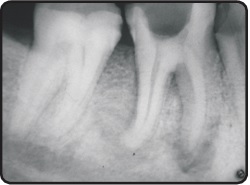

Endodontic Therapy: We specialize in the diagnosis and treatment of infected, inflamed or necrotic pulp, utilizing advanced techniques following the principles of minimal invasive dentistry.